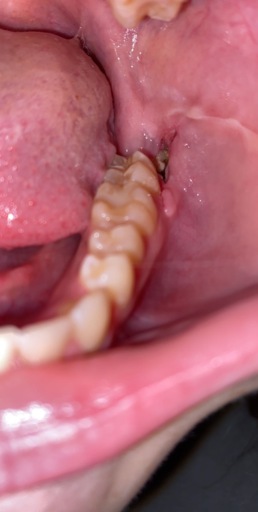

What is the procedure for impacted Canines that are at the top only for both canines and they are in the top of the gums on the outside (not in palette). I have an X-ray. ITS FOR MY DAUGHTER... 12 years old and 2 months.

Impacted Canines